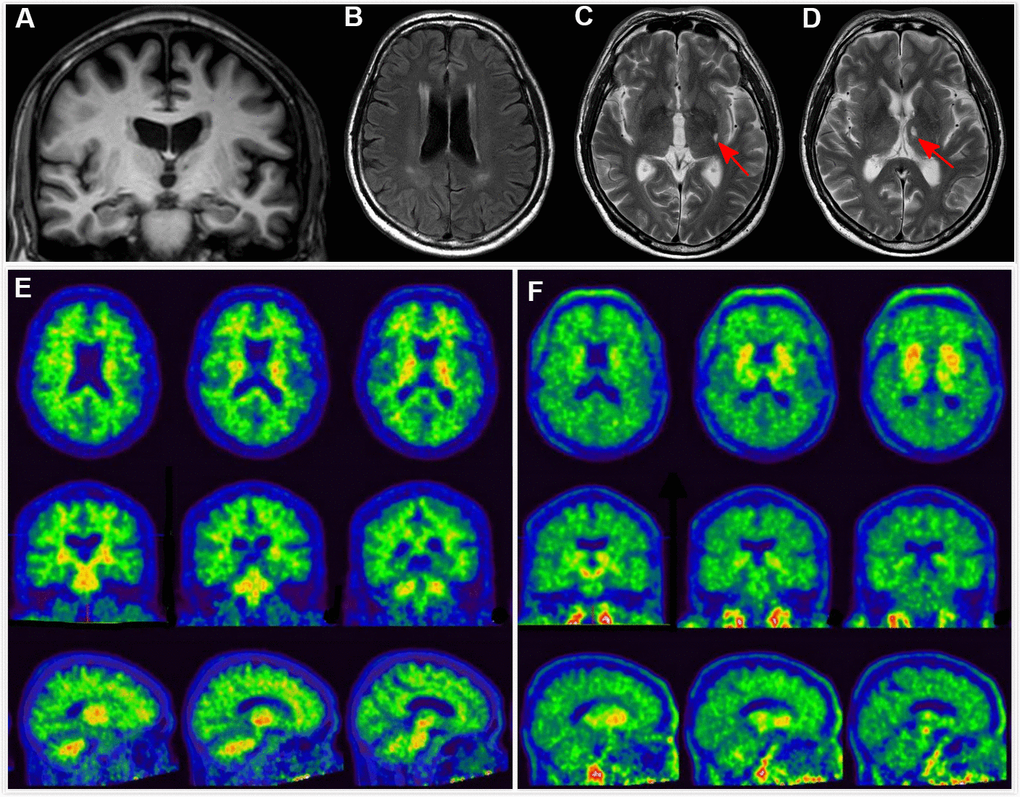

Although there is still no definitive pharmacological treatment approved for preventing subjects with prodromal AD from progressing to AD with dementia, emerging studies have shown promising results of various strategies in slowing cognitive decline at an early or prodromal stage [20, 21]. Moreover, making a diagnosis of prodromal AD among subjects with MCI is also important for the sake of providing a correct diagnosis of the MCI syndrome, for prognostication, as well as for recruiting prodromal AD subjects into preventive clinical trials. Recent trials for AD have shifted to targeting subjects from the dementia stage to the prodromal or even preclinical stage [22]. Although PET or CSF analyses are now available to detect A+T+ at the early stage and have been used to recruit prodromal or preclinical AD subjects into clinical trials, availability of an easier method in detecting A+T+ subjects will help to reduce the cost of conducting clinical trials. Among MCI subjects, AD-RAI (≥ 0.5) achieved a high NPV of 91.30%, hence a “negative” AD-RAI will first help to rule out subjects without AD. For subjects with a “positive” AD-RAI, further investigations (i.e. PET or CSF analyses) can be arranged to confirm the diagnosis of prodromal AD. Moreover, using MRI as an initial investigation in MCI is also useful in ruling out other common brain lesions, e.g. cerebral small vessel disease (Figure 1) or other rare yet potential reversible causes, e.g. normal pressure hydrocephalus, brain tumor.

Figure 1. Clinical utility of AD-RAI in MCI subjects. A 68-year-old man with 11 years of education had complaints of memory decline for over 3 years. Z-score in Trial 4 of HKLLT was -1.94 SD (≤ -1 SD, i.e. MCI). Visual MTA rating score on MRI was 1 (≥ 1), (A) which was suggestive of AD. However, HV measures yielded conflicting results, with HF of 0.47% (> 0.41%) and raw HV of 7.38ml (> 6.07mL) suggestive of non-AD. FLAIR and T2-weighted sequences showed periventricular white matter hyperintensity and two subcortical lacunes (red arrows) (B–D). AD-RAI was only 0.11 (< 0.5) also suggestive of non-AD. Subsequent PIB PET (E) and T807 PET (F) showed negative results (i.e. A-T-), supporting the finding of AD-RAI. The MCI syndrome and mild MTA might be associated with cerebral SVD (i.e. vascular MCI associated with SVD).